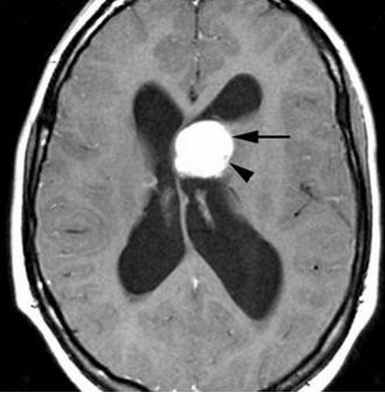

При МРТ доброкачественные астроцитомы чаще выглядят однородными, хотя возможна неоднородность в связи с кальцинатами (до 20% случаев) и микрокистозной дегенерацией. Границы опухоли четкие. Вазогенный отек выражен только при низкодифференцированном подтипе. Астроцитома может вовлекать кору мозга и напоминать острый ишемический инсульт. Различать их при МРТ помогает отчетливо клиновидная форма при инсульте, совпадающая с бассейном кровоснабжения. Нередко при МРТ головного мозга встречаются “кистозные” астроцитомы, когда сама опухоль имеет небольшие размеры, а прилежащая ликворная киста значительно больше ее самой. Анапластические астроцитомы на МРТ хорошо усиливаются при контрастировании, доброкачественные астроцитомы усиливаются при МРТ с контрастированием примерно в 40% случаев. Изредка встречаются первично-множественные астроцитомы. Гигантоклеточная внутрижелудочковая астроцитома встречается только при туберозном склерозе. При МРТ она имеет типичное расположение и хорошо контрастируется.